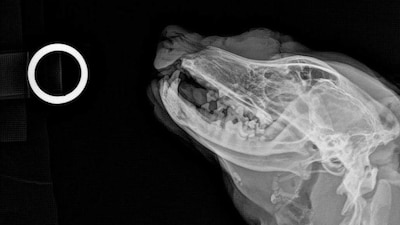

Se trata de una agresión contra un perrito, a quien le detonaron un fuego pirotécnico en el rostro y parte del cuerpo. Los hechos ocurrieron la noche del pasado 24 de diciembre en calles de la colonia Efrén Capiz.

A través de denuncias anónimas, se supo que el 'lomito' fue herido de manera intencional por un cuete que le tronaron en el rostro.

El caso se difundió en redes sociales donde se mostraba al perrito, que estaba en situación de calle, lesionado gravemente.

Una integrante de la asociación animalista Ami-Dogs atendió el caso y trasladó al 'lomito' a recibir atención urgente a una clínica veterinaria donde fue atendido, pero donde lo reportan delicado.